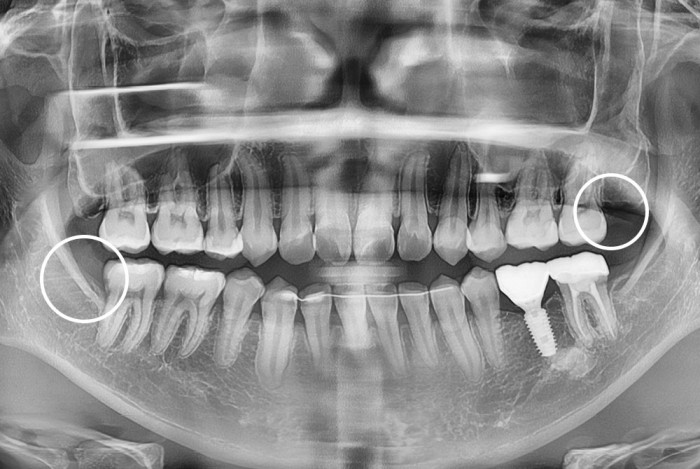

[사랑니] 사랑니

치료후 : 2023-02-15

세종치과는 구강악안면외과학 박사이신 원장님이 발치하는 치과입니다.